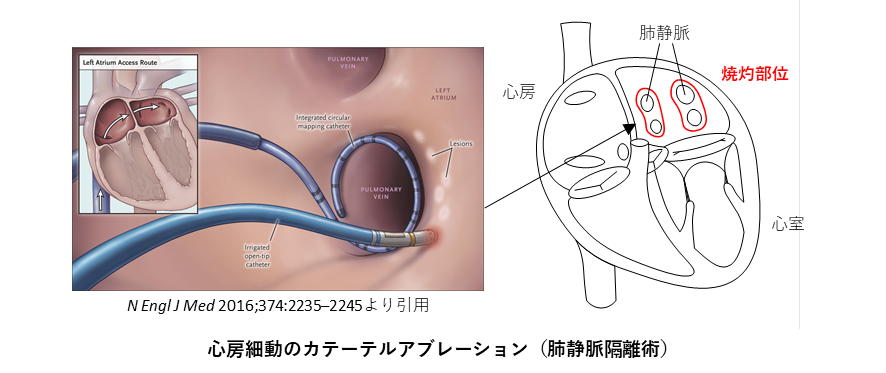

心房細動のカテーテルアブレーション

発作性心房細動の約90%が左心房にある肺静脈が原因といわれています。ここから異常な電気信号(トリガー)が発生し、心房内に伝わることで心房細動が引き起こされると考えられており、心房細動アブレーションはこの電気信号が心房内に伝わってこないように、肺静脈入り口の周囲を通電・焼灼して電気的な交通を遮断します(上図)。この手術は肺静脈隔離術といいます。

また心房細動は肺静脈のみならず、右心房にある上大静脈が原因で発症するものもあれば、頻度は少ないものの心房内からの異常信号で発症することもあります。その場合、追加の治療が必要になります。